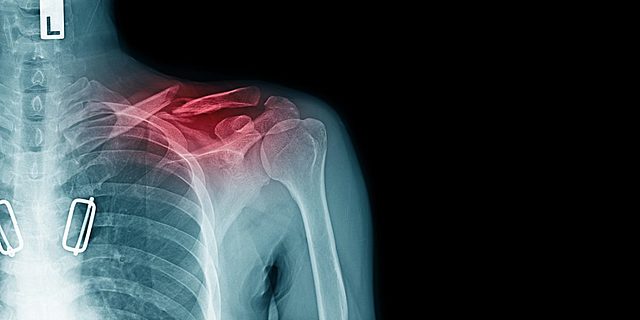

• Clavicle Fracture

Clavicle Fracture

In 8th grade I broke my collarbone also known as the clavicle playing football in recess with my friends. I was running with the ball and another student tries to tackle me and I land on my shoulder pushing against my clavicle and causing it to snap